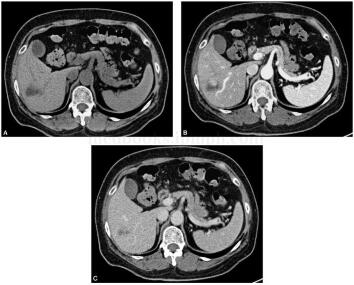

患者,男性,57岁,主诉:乏力1个月,发现肝脏占位1周。病来患者自觉乏力,无发热,无腹痛、腹胀,无血及黑便,体重未见下降。既往否认肝炎、结核病史。查体:皮肤及巩膜无黄染,腹软,无压痛,无反跳痛及肌紧张,未触及局部包块,肝脾肋下未及,墨菲征(-),肝区叩痛(+),移动性浊音(-)。AFP:8ng/ml。CT增强检查如图1。

图1 CT增强扫描:术前考虑肝脏炎性假瘤。CT平扫显示肝S6段稍低密度灶,边界模糊,中心见更低密度区,增强扫描后动脉期呈结节样强化,静脉期结节强化减弱,略低于周围肝实质,增强各时相病变内见未强化区